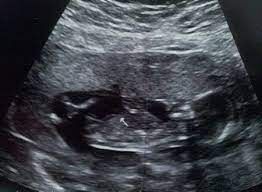

حيث تداول عدد من رواد مواقع التواصل الاجتماعي مقطع فيديو يروي قصة عظة من حمل إحدى السيدات، حيث يتضمن الفيديو أن هناك سيدة كانت حاملا وخلال فترة الحمل اكتشفت أن بداخل السونار كرة سوداء طمساء لا تحمل أي معالم، ونصحها الكثير من الأطباء بـ الإجـ ـهاض.

ولكن صممت الأم ألا تجـ ـهض جنينها، وحمدت الله – عز وجل – على تلك النعمة التي يتمناها العديد وبالفعل استكملت الحمل، وكانت المفاجأة عند الولادة حيث أنها وضعت طفلة شديدة الجمال شعرها طويل للغاية كان ملفوف حول جسدها مما أعطاهم الإيحاء أن هناك تشوه للجنين في السونار